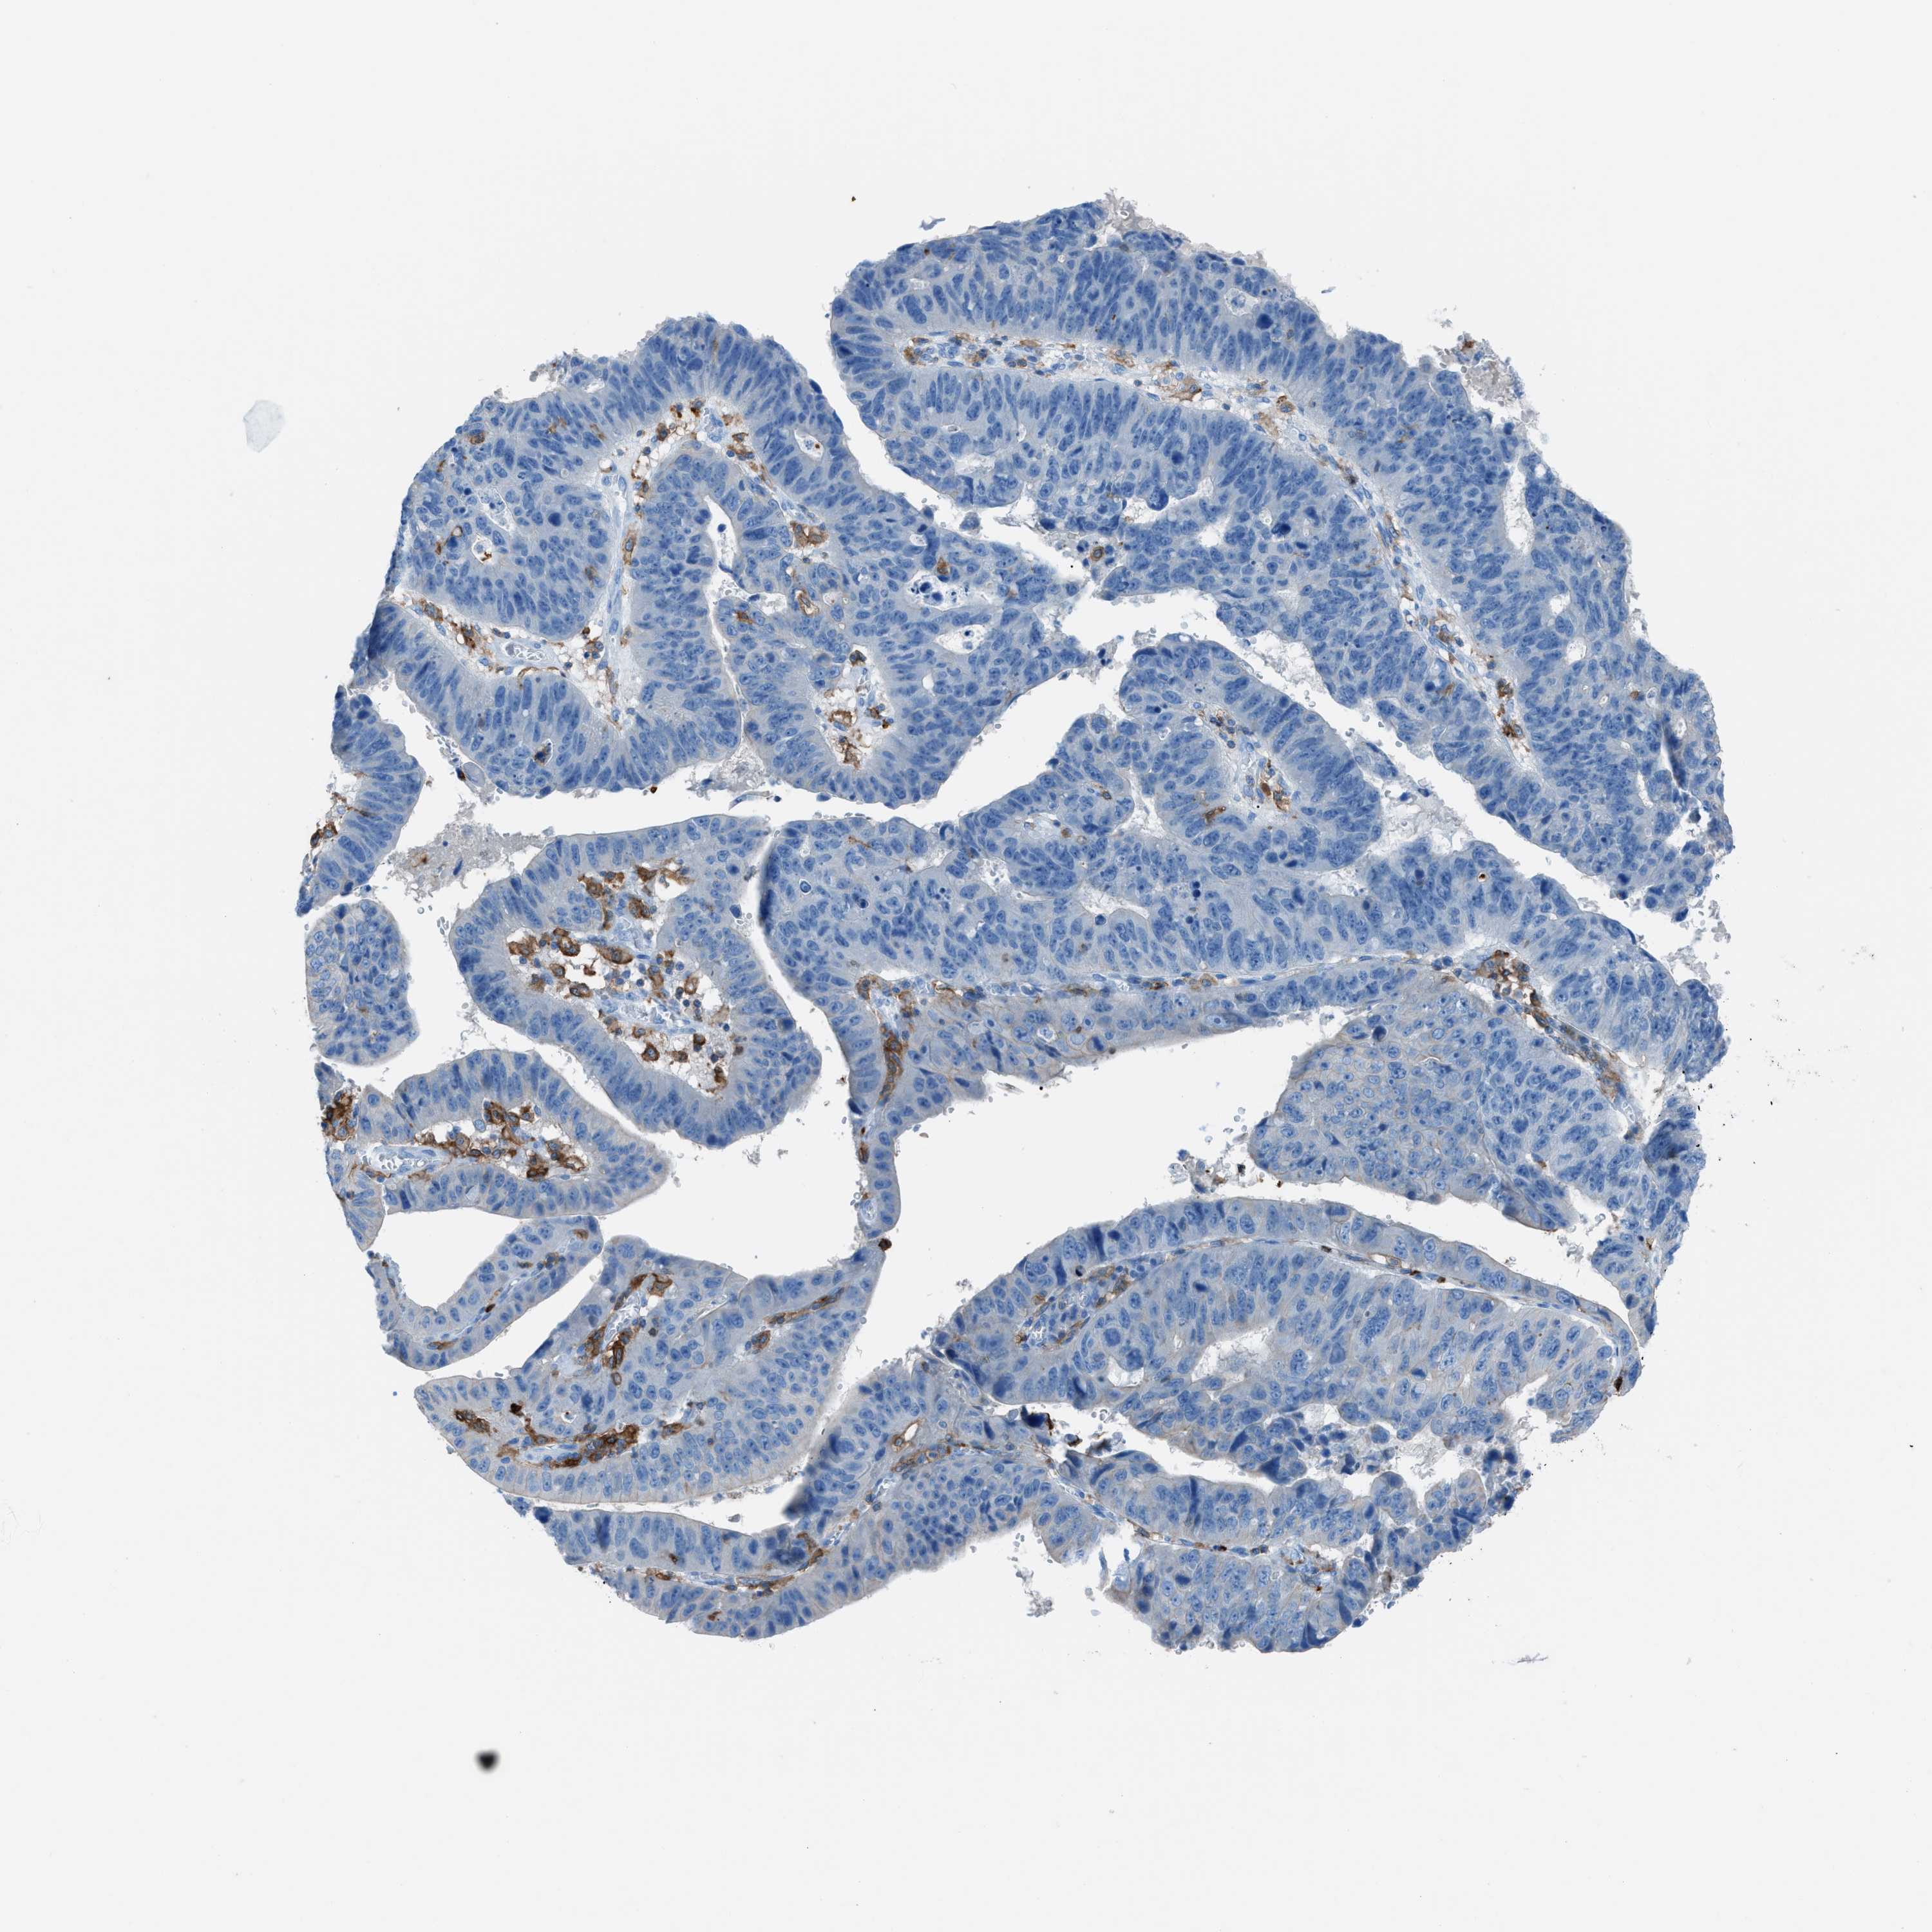

STOMACH CANCER - Protein expressioni

A mouse-over function shows sample information and annotation data. Click on an image to view it in a full screen mode. Samples can be filtered based on level of antibody staining by selecting one or several of the following categories: high, medium, low and not detected. The assay and annotation is described here.

Note that samples used for immunohistochemistry by the Human Protein Atlas do not correspond to samples in the TCGA dataset.

Antibody stainingi

Antibody staining in the annotated cell types in the current human tissue is reported as not detected, low, medium, or high, based on conventional immunohistochemistry profiling in selected tissues. This score is based on the combination of the staining intensity and fraction of stained cells.

Each image is clickable and will lead to virtual microscopy that enables deeper exploration of all samples and also displays staining intensity scores, fraction scores and subcellular localization as well as patient and tissue information for each sample.

Antibody HPA008877

Antibody HPA016894

Adenocarcinoma, NOS